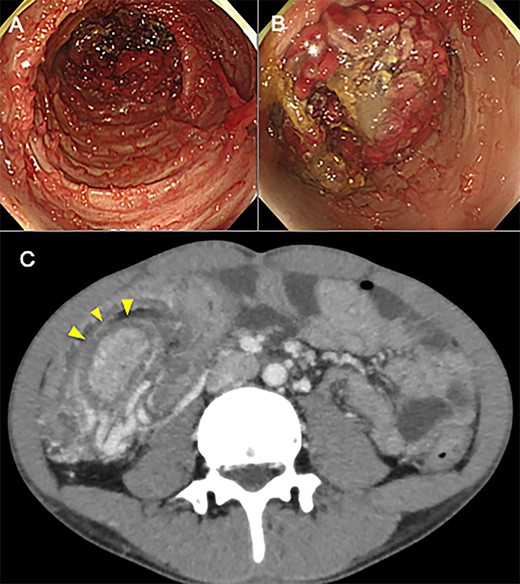

An 18-year-old man came to our hospital having initially sought treatment at the age of 16 for bloody stool. Colonoscopy revealed multiple inflammatory polyps less than 1 cm throughout the colon and the patient was diagnosed with UC by biopsy. He was initially treated with tacrolims to induce remission and was subsequently administered 5-aminosalycilic acid orally for maintenance of remission. A year later, surveillance colonoscopy failed completely because polyps in the transverse colon closed the lumen. Having no abdominal pain or the other symptoms, and no abnormalities in laboratory values, he did not undergo detailed examination at that time. Thereafter, surveillance colonoscopy the following year also failed to show the total colon, (Fig. 1A and B) a computed tomography (CT) was performed. The CT revealed elongated mass lesion in the area of the transverse colon, and the patient was diagnosed with colonic intussusception (Fig. 1C). Because he still had no symptoms, nor laboratory abnormalities, we performed to endoscopic enema reduction. Enema reduction had failed because air had passed through the lead-point of intussusception in transverse colon. Accordingly, the patient underwent elective laparoscopic total colectomy for treatment of the intussusception with UC. The operative finding revealed inversion of the transverse colon into the distal transverse colon. Histology showed widespread inflammatory polyps with no evidence of neoplasia (Fig. 2A and B). The patient’s postoperative course was uneventful, and he was discharged 28 days after surgery.

(A) Gross feature of surgical resection specimen. The proximal transverse colon has invaginated into the distal transverse colon. (B) Opened surgical specimen. Numerous inflammatory polyps spread throughout the entire colon.